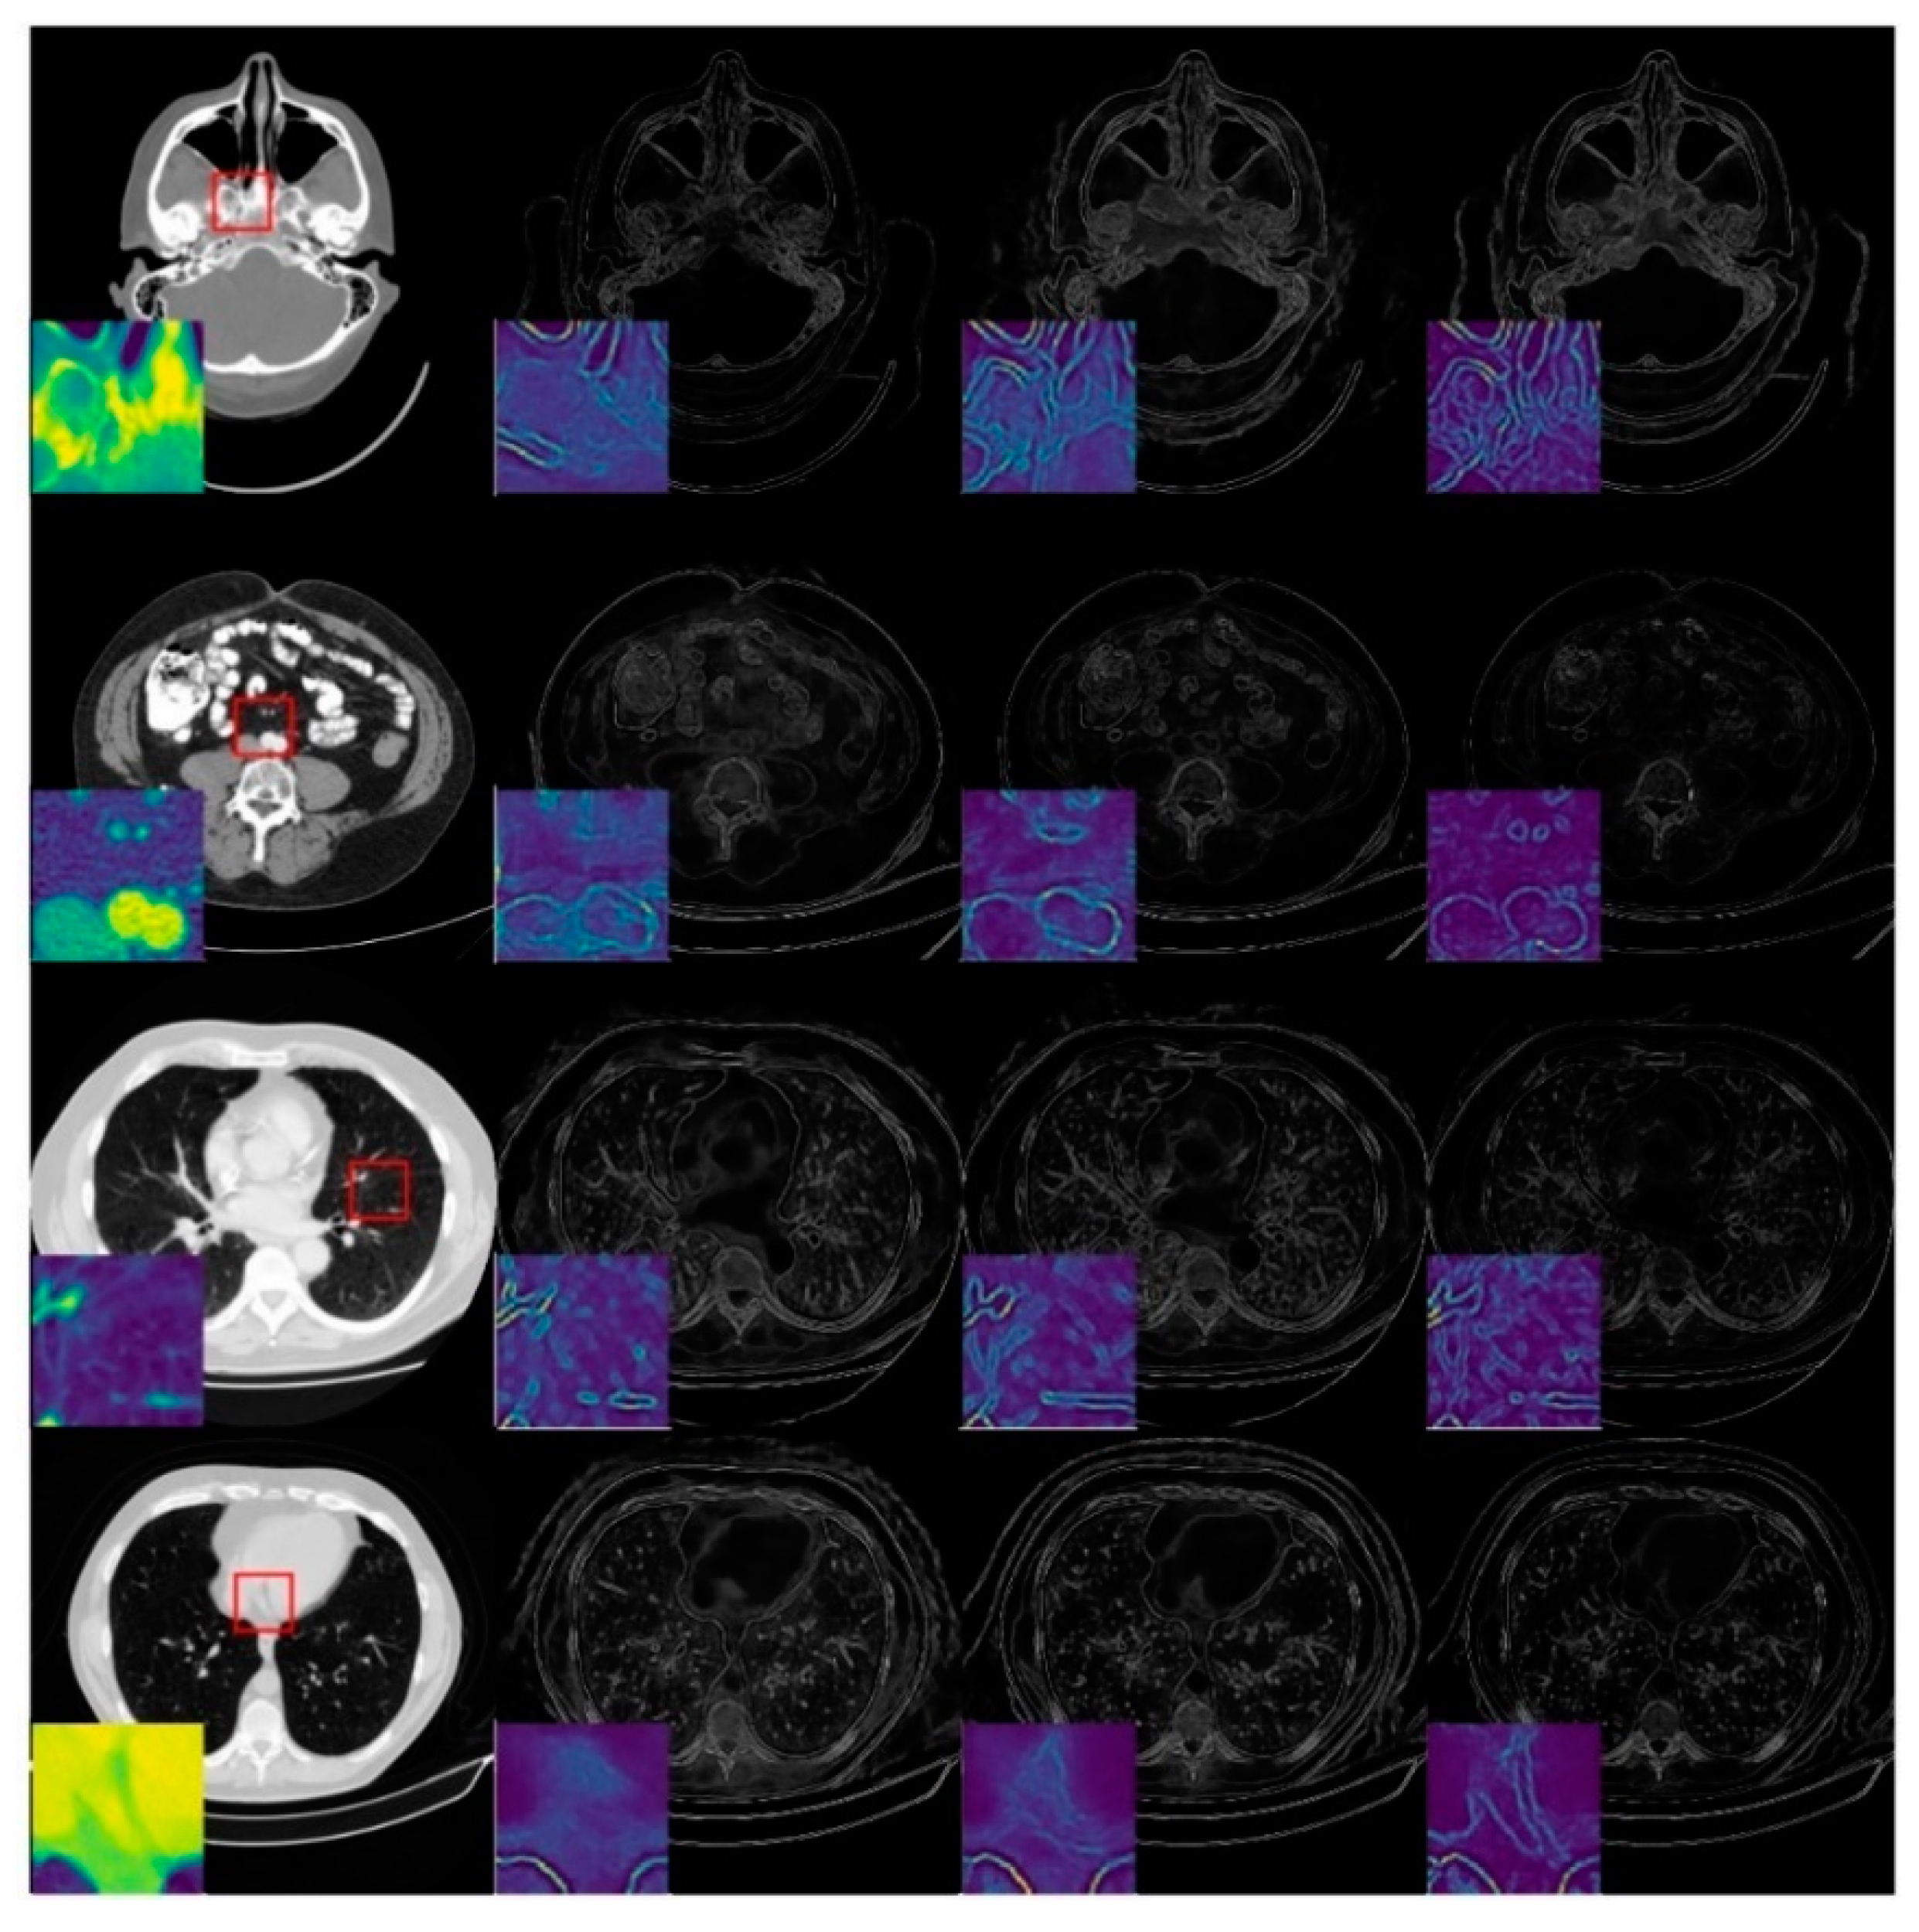

To investigate the degradation perception of the image-domain module, we compared the predicted critical-map of the spatial-attention block for the same image with different degradation levels, as shown in Figure 7. The first column is the ideal CT image, whilst the second, third and fourth columns represent the predicted critical-maps at 60 views, 120 views and 240 views, respectively. We zoomed in on the red square area and displayed it in color to observe the textual details. The edge information of the critical-map increases as the degradation decreases, which indicates that the reconstructed values of the contours are generally inaccurate and the later refining block should enhance the detail recovery and reconstruction. In the case of the large degradation level, the critical-map of the image is blurry, indicating that there are still small artifacts interfering in the flat region, which should be further removed in the refining block to improve the overall intensity recovery.

Figure 7.

Examples of predicted critical-maps at 60 views, 120 views and 240 views.

Experimental results shown in Figure 6 indicate that the proposed frequency-attention block was able to capture the characteristics of a different degradation level in the frequency domain. This result coincides with the previous conclusion of Figure 1, which demonstrates that the frequency-attention block is able to differentiate degradation levels and adaptively adjust the frequency-attention-map to better guide the reconstruction block. In addition, as shown in Figure 7, the spatial-attention block can sense the specificity of different degradation levels in the image domain, and give the pixels that should be focused on the later reconstruction to further map the ground truth image.